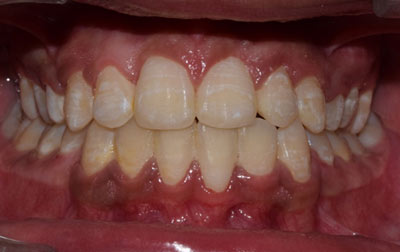

Smile makeover:

Radiating confidence through a beaming smile can truly uplift your spirits. A captivating smile holds significant sway in social and professional spheres, enhancing your overall appeal. However, numerous individuals refrain from revealing their teeth in public or photographs due to personal dissatisfaction. If you find yourself in this category, why not consider allowing us to assist you in attaining the smile you've always envisioned? Embark on a journey toward your ideal smile with our transformative smile makeover. A smile makeover transcends the mere resolution of dental issues as they arise. It constitutes a holistic plan to rejuvenate your smile, intricately tailored to complement your distinct facial features and aesthetic inclinations. The outcomes are nothing short of remarkable—both in terms of your visual transformation and the surge of newfound confidence you'll experience.